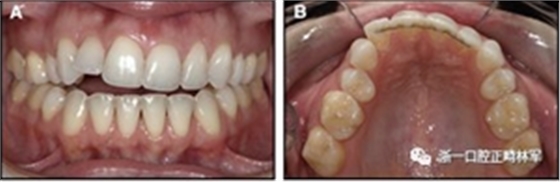

隨著時(shí)間的推移,全維度弓絲及其表達(dá)的牙齒間扭矩差異顯著改善(圖17)。明智的鄰間減少之后,間隙關(guān)閉擴(kuò)大接觸面,消除不美觀的黑三角。在脫粘之前也校正了牙齒排列和牙弓形態(tài)(圖18)。

圖18.脫粘后的最終圖像:A,正面視圖; B,咬合面視圖。 進(jìn)一步的牙齒移動(dòng)以糾正輕度前牙開(kāi)合被認(rèn)為不符合患者的最佳利益。